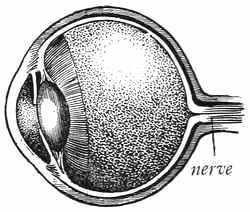

Sight is one of the greatest blessings we have. Think how dreadful it is to be blind. If you take care of your eyes, there is no reason why you should be blind; but if you do not take care of your eyes, there is a possibility that you may lose your sight. Most of the blind people in the world became blind because their eyes were not given proper care, and most of this lack of care happened when these people were babies.

Many of the diseases that affect the eyes are catching. They are not carried through the air, but are transmitted by the use of a towel or handkerchief used by someone who had the disease. Never use the towel or handkerchief that another has used.

Germs may be rubbed into the eyes. Keep your hands away from your eyes. Your hands may have disease germs on them, and when you rub your eyes you may put the disease germs into them.

Many boys and girls ruin their eyes by making them do too much work. They do this by reading in a poor light, by reading where the light strikes into the eyes, or by reading in a bad position, as when in bed or lying down. When you are reading, drawing, or doing any work with the eyes, always have the best light possible, which means that the light should fall on your book or work over your left shoulder. If you are only reading, it does not make much difference which shoulder the light comes over, provided it comes from behind. If you are writing or drawing, and the light comes over your right shoulder, it makes the shadow of your hand fall just where you want to see.

Another way of working your eyes too much is by trying to see when the eyes are not focused right. Sometimes people are said to be near-sighted, because they cannot see very well at a distance. This is due to the fact that the[58] eyeball is too long, so that the lens does not cause the rays of light to focus on the retina. Some people are called far-sighted. This means that they can see well at a distance, but that it is hard for them to see things close to them. Far-sighted children can usually see things near by, but they do this by making the muscle that rules the lens of the eye work too hard.

Probably your teacher has a test chart and can tell you whether your eyes are properly focused. If your eyes are not focused right, that is, if you cannot see the line of letters marked 20 when you are twenty feet from this chart, there is something wrong with your eyes. In that case, you are not only injuring them by trying to study, but you are hurting the whole body by overworking a part of it. If you cannot see the letters on the test card clearly at a distance of twenty feet, ask your father to send you to a specialist who will fit you with the proper glasses or will treat your eyes so that you can see well.